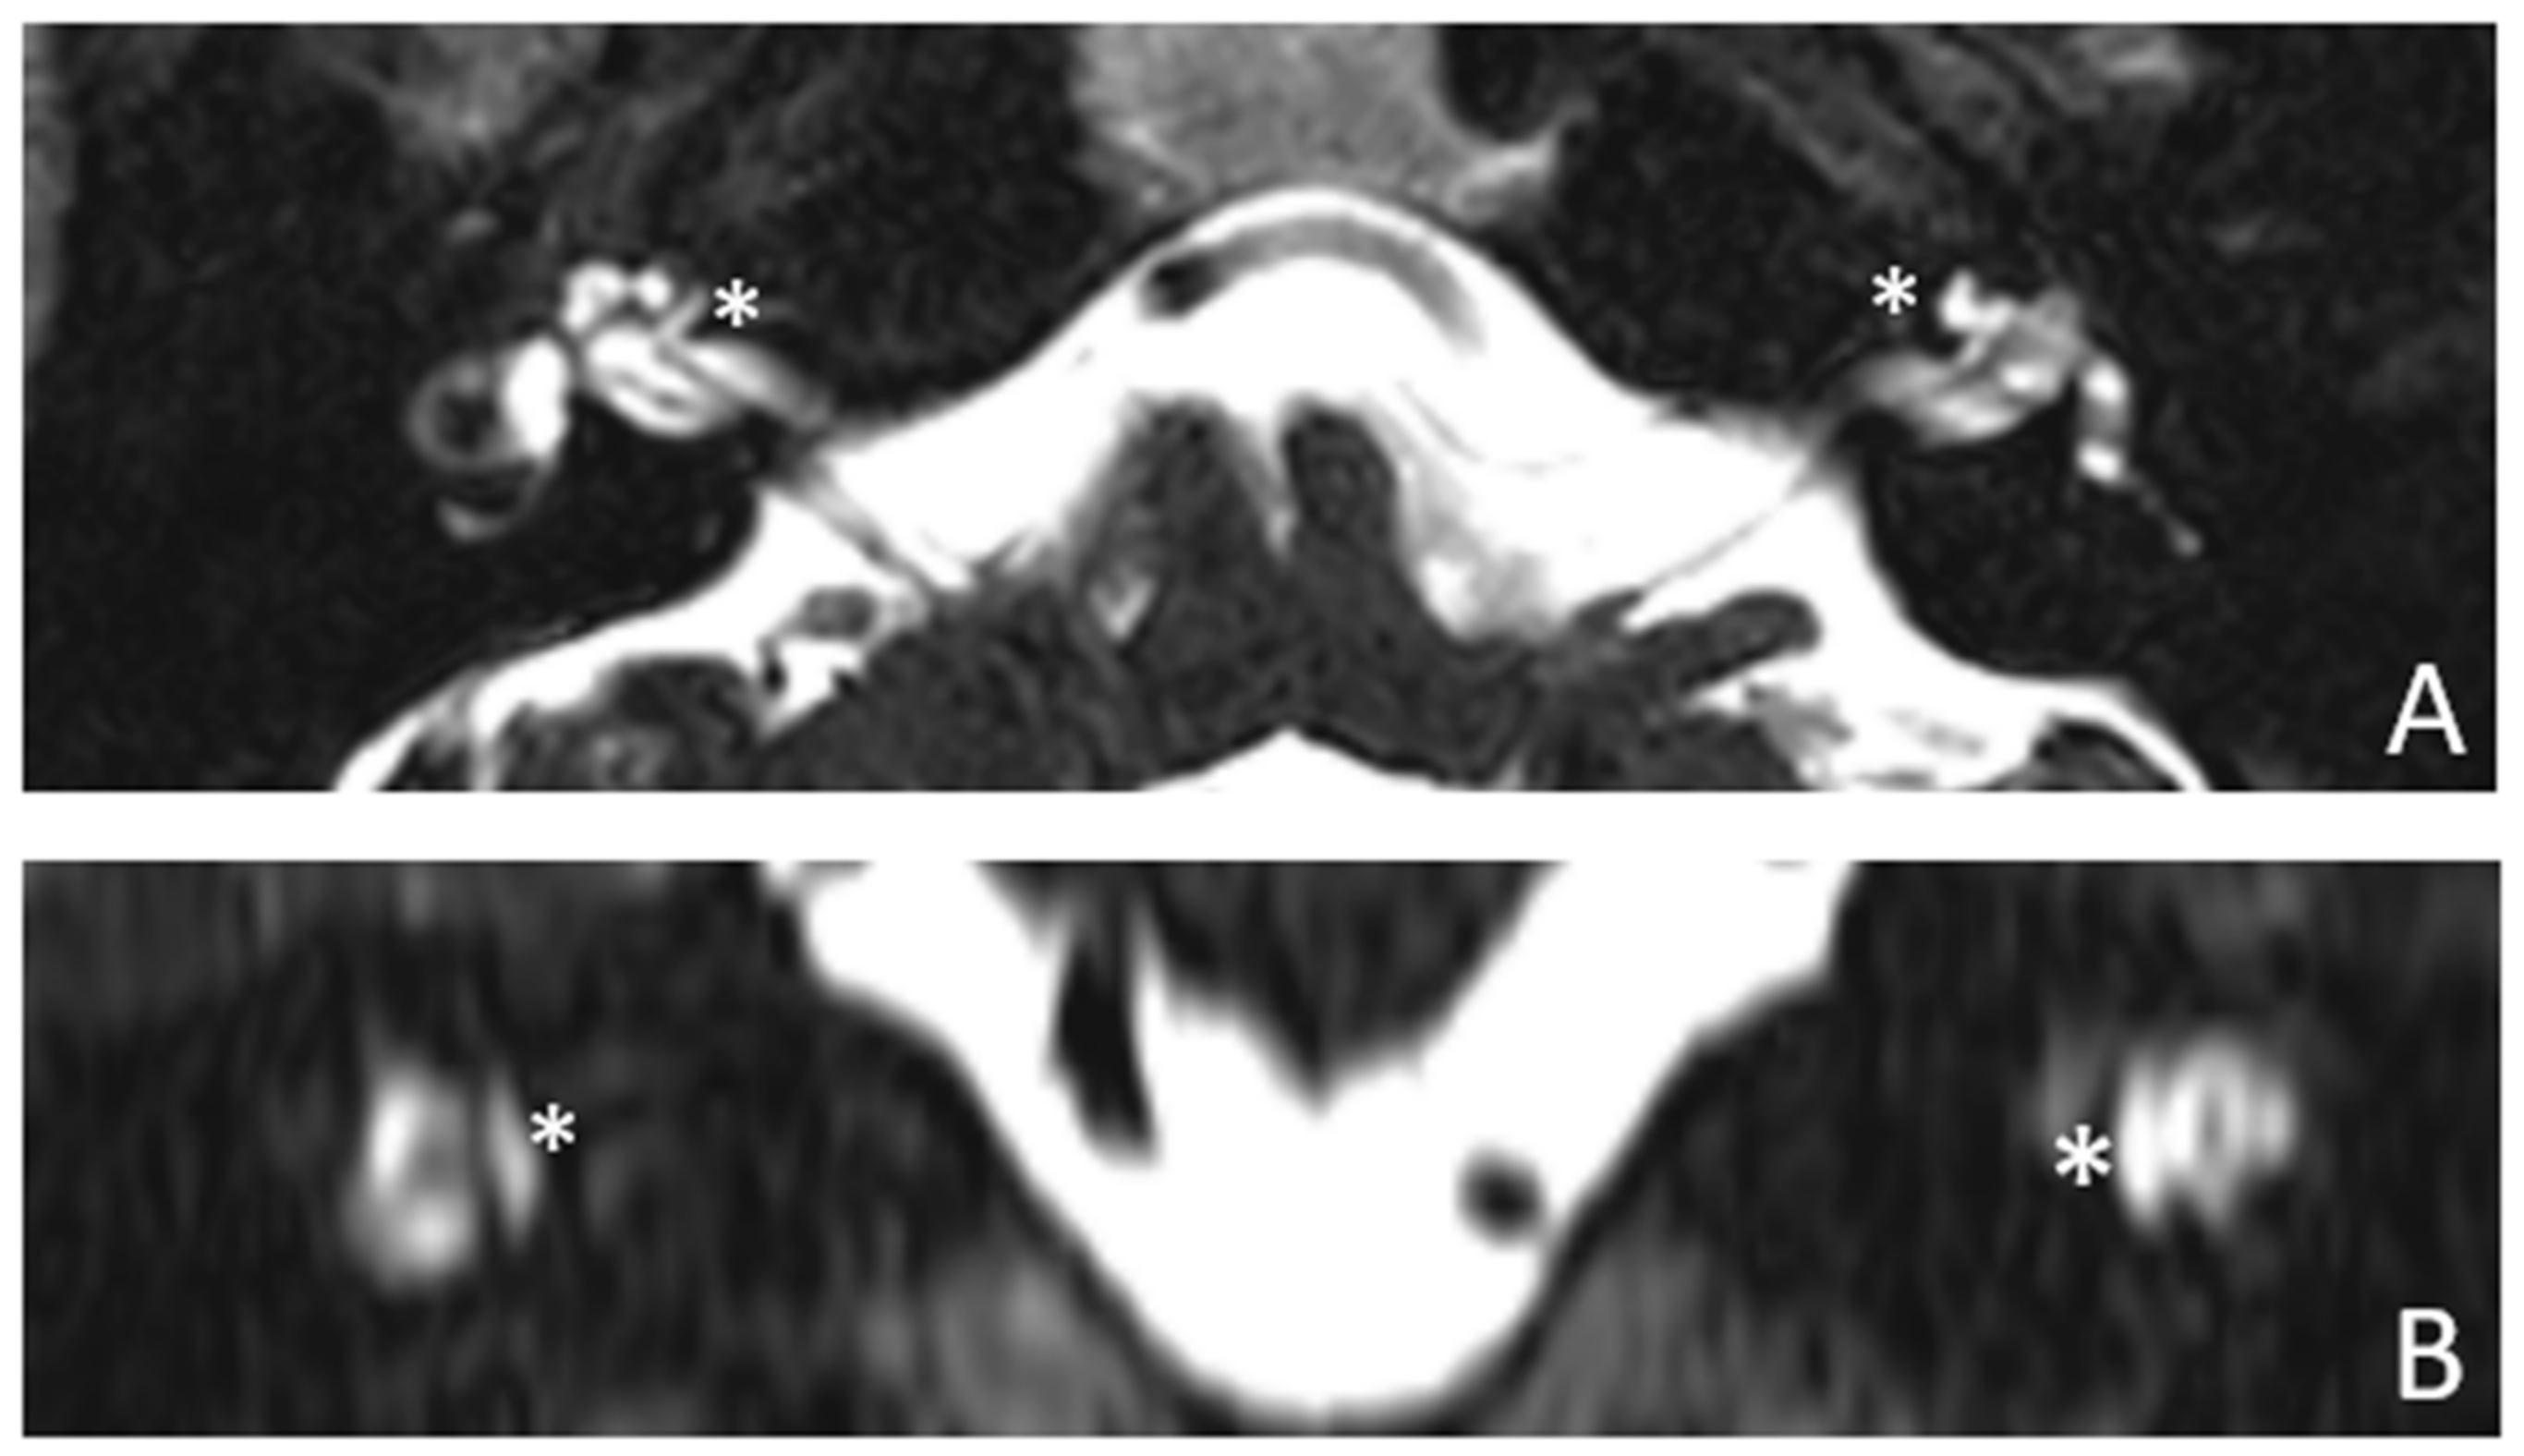

Figure 4.

MR images of patient #2 with osteogenesis imperfecta. MR cisternography: (A), axial plane; (B), coronal plane. Note the fluid-signal in the newly formed cavities (white asterisk).

Patient #2, affected by OI-type I (COL1A1 mutation). MHL since diagnosis. Bone threshold was similar in both ears, but PTA was worse in the right ear with a larger ABG. HL progressed, but the difference between the two sides was maintained. The patient was fitted with conventional hearing aids bilaterally. Stapes surgery was not performed because of the radiological aspect (Figure 3 and Figure 4): a large cavity is present bilaterally and diffused communication between the cavity and the cochlea is evident.